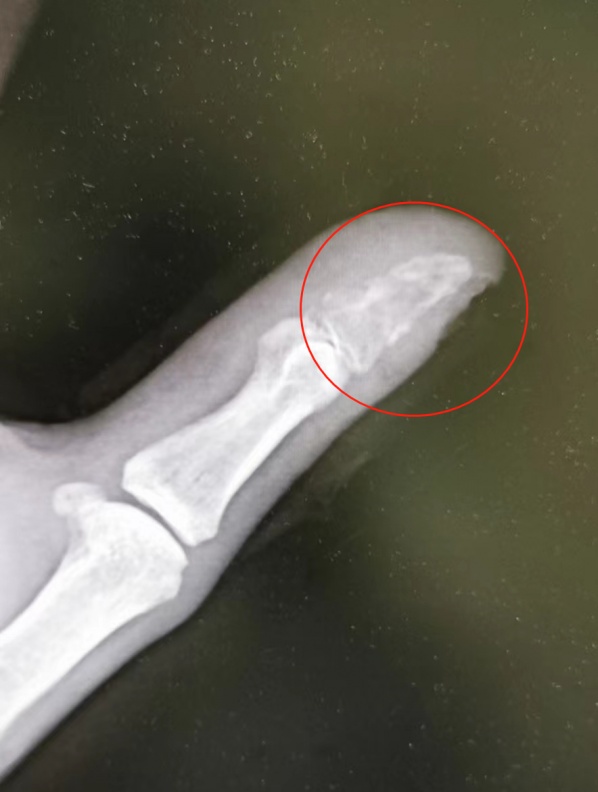

患者拇指末节指骨被细菌侵蚀“吃空”。

一周后,蒋先生发现手指伤口红肿,便到附近医院就诊。医生发现蒋先生伤口有感染,为其清创换药,并叮嘱他按时到医院换药,但怕麻烦的蒋先生一去不返,继续在家自行消毒处理。5月底,蒋先生不仅伤口没长好,手指还疼得不敢触碰,这才来到武汉市第四医院手外科门诊。经检查,蒋先生伤口感染严重,拍片显示拇指末节指骨也被细菌侵蚀“吃空”,存在截指的风险。

“目前通过手术已将患者感染控制,尽力保住了患者的拇指,后期将进行植骨手术治疗。”严立主任提醒,日常生活中,不要随意撩拨不熟悉的宠物,一旦被宠物咬伤,应尽快到医院接种狂犬疫苗并处理伤口,千万不要盲目自行处理。(长江日报记者武叶 通讯员杨红 李善庆)